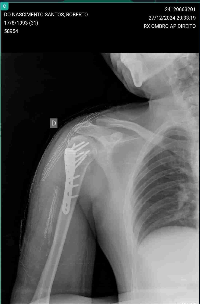

A moto danificou bastante e ele teve uma fratura no braço e está em Goiânia para realização de uma cirurgia, essa vaquinha tem o intuito de levantar fundos para ajuda-lo no custeio do concerto da moto, e ajuda-lo financeiramente as custear seus remédios.